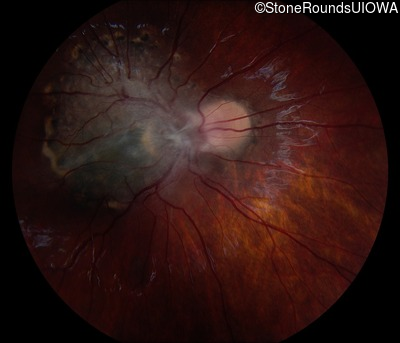

This 9 year old male was noted to have some crossing of his eyes at 2 months of age and the eye exam which followed identified a retinal lesion in the right eye. When he was six years old an epiretinal membrane was noted in his left eye. Two years later it was decided that it was a thin hamartoma in that eye as well. He underwent neuroimaging at age 7 which identified bilateral acoustic neuromas.

| Age at visit: 7 years |

| Age at visit: 8 years |